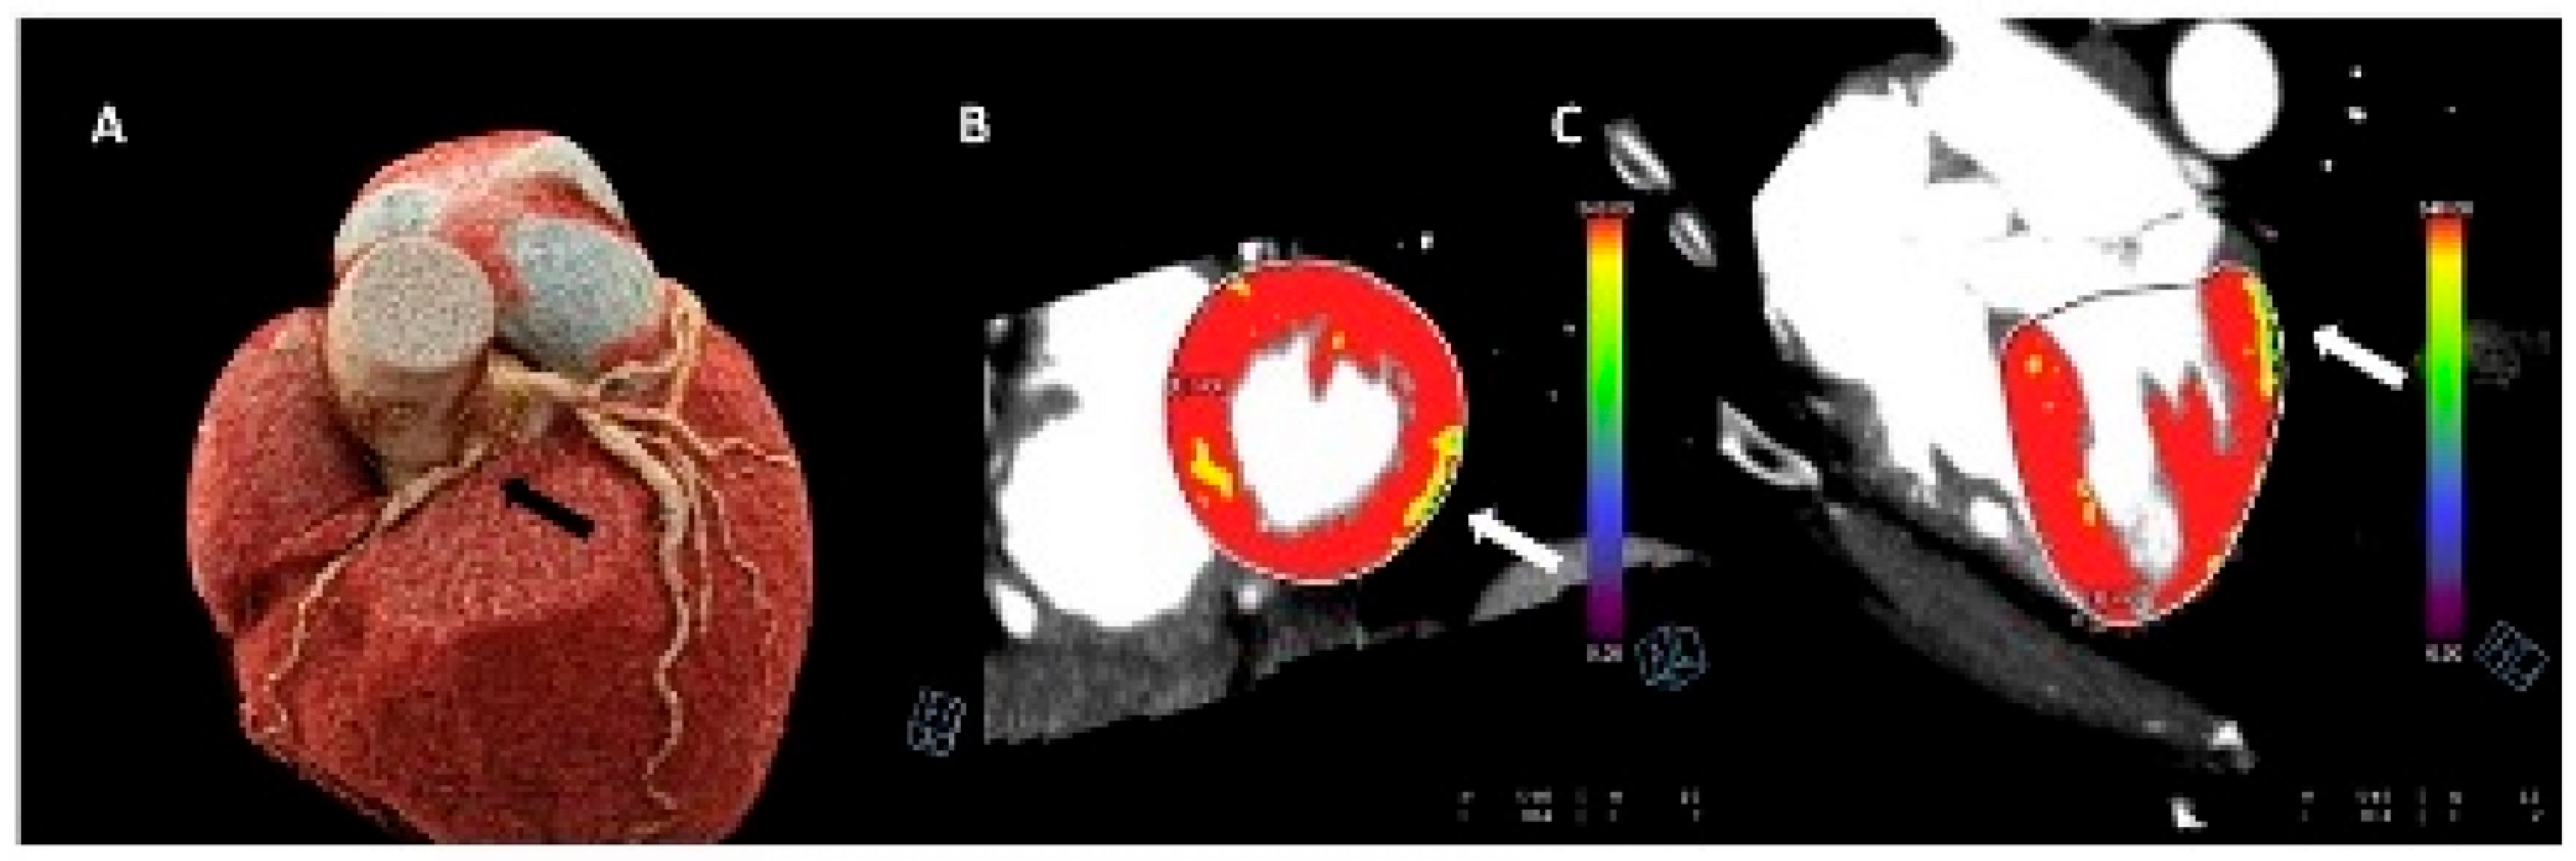

5. Stress Computed Tomography Perfusion Imaging

5.1. Introduction

5.2. Protocol

5.3. Limitations